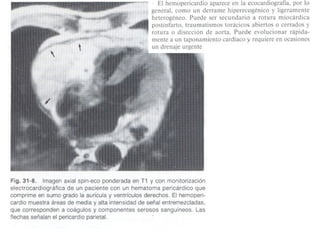

Derrame pericárdico corazón grande, globular, con una cardiomegalia exagerada en relación a la vascularidad pulmonar

El estudio de la grasa epicárdica